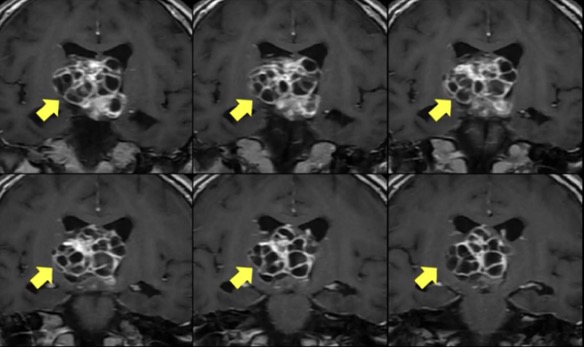

术前核磁共振显示脑深部巨大肿瘤,压迫下丘脑和脑干。本文图均为 受访者 供图

一个巨大的肿瘤盘踞在18岁女生雯雯(化名)的脑部,压迫着下丘脑和脑干。这个直径超过4厘米的肿瘤内含十几个囊肿,像石榴籽一样相互包裹、挤压,而且质地很韧,混有骨质成分。

“这么大的肿瘤,这么‘险要’的位置,不仅会堵住脑脊液循环、引起颅内压增高,还会直接压迫周边的神经和血管,引起昏迷、失明、大小便失禁和多脏器功能代谢紊乱等症状,危及生命。如果手术,同时在下丘脑和脑干这两个手术禁区‘耍刀’,无异于虎口拔牙,任何医生都没十足把握手术一定成功。”华山医院金垂体医疗团队负责人赵曜表示,雯雯的脑肿瘤几乎挤满整个脑深部的中央区域,国内外文献也很少见到在这个位置长这么大肿瘤的报道,“做了那么多年医生,看过那么多脑肿瘤病人,我还是第一次看到这么夸张的瘤子。”